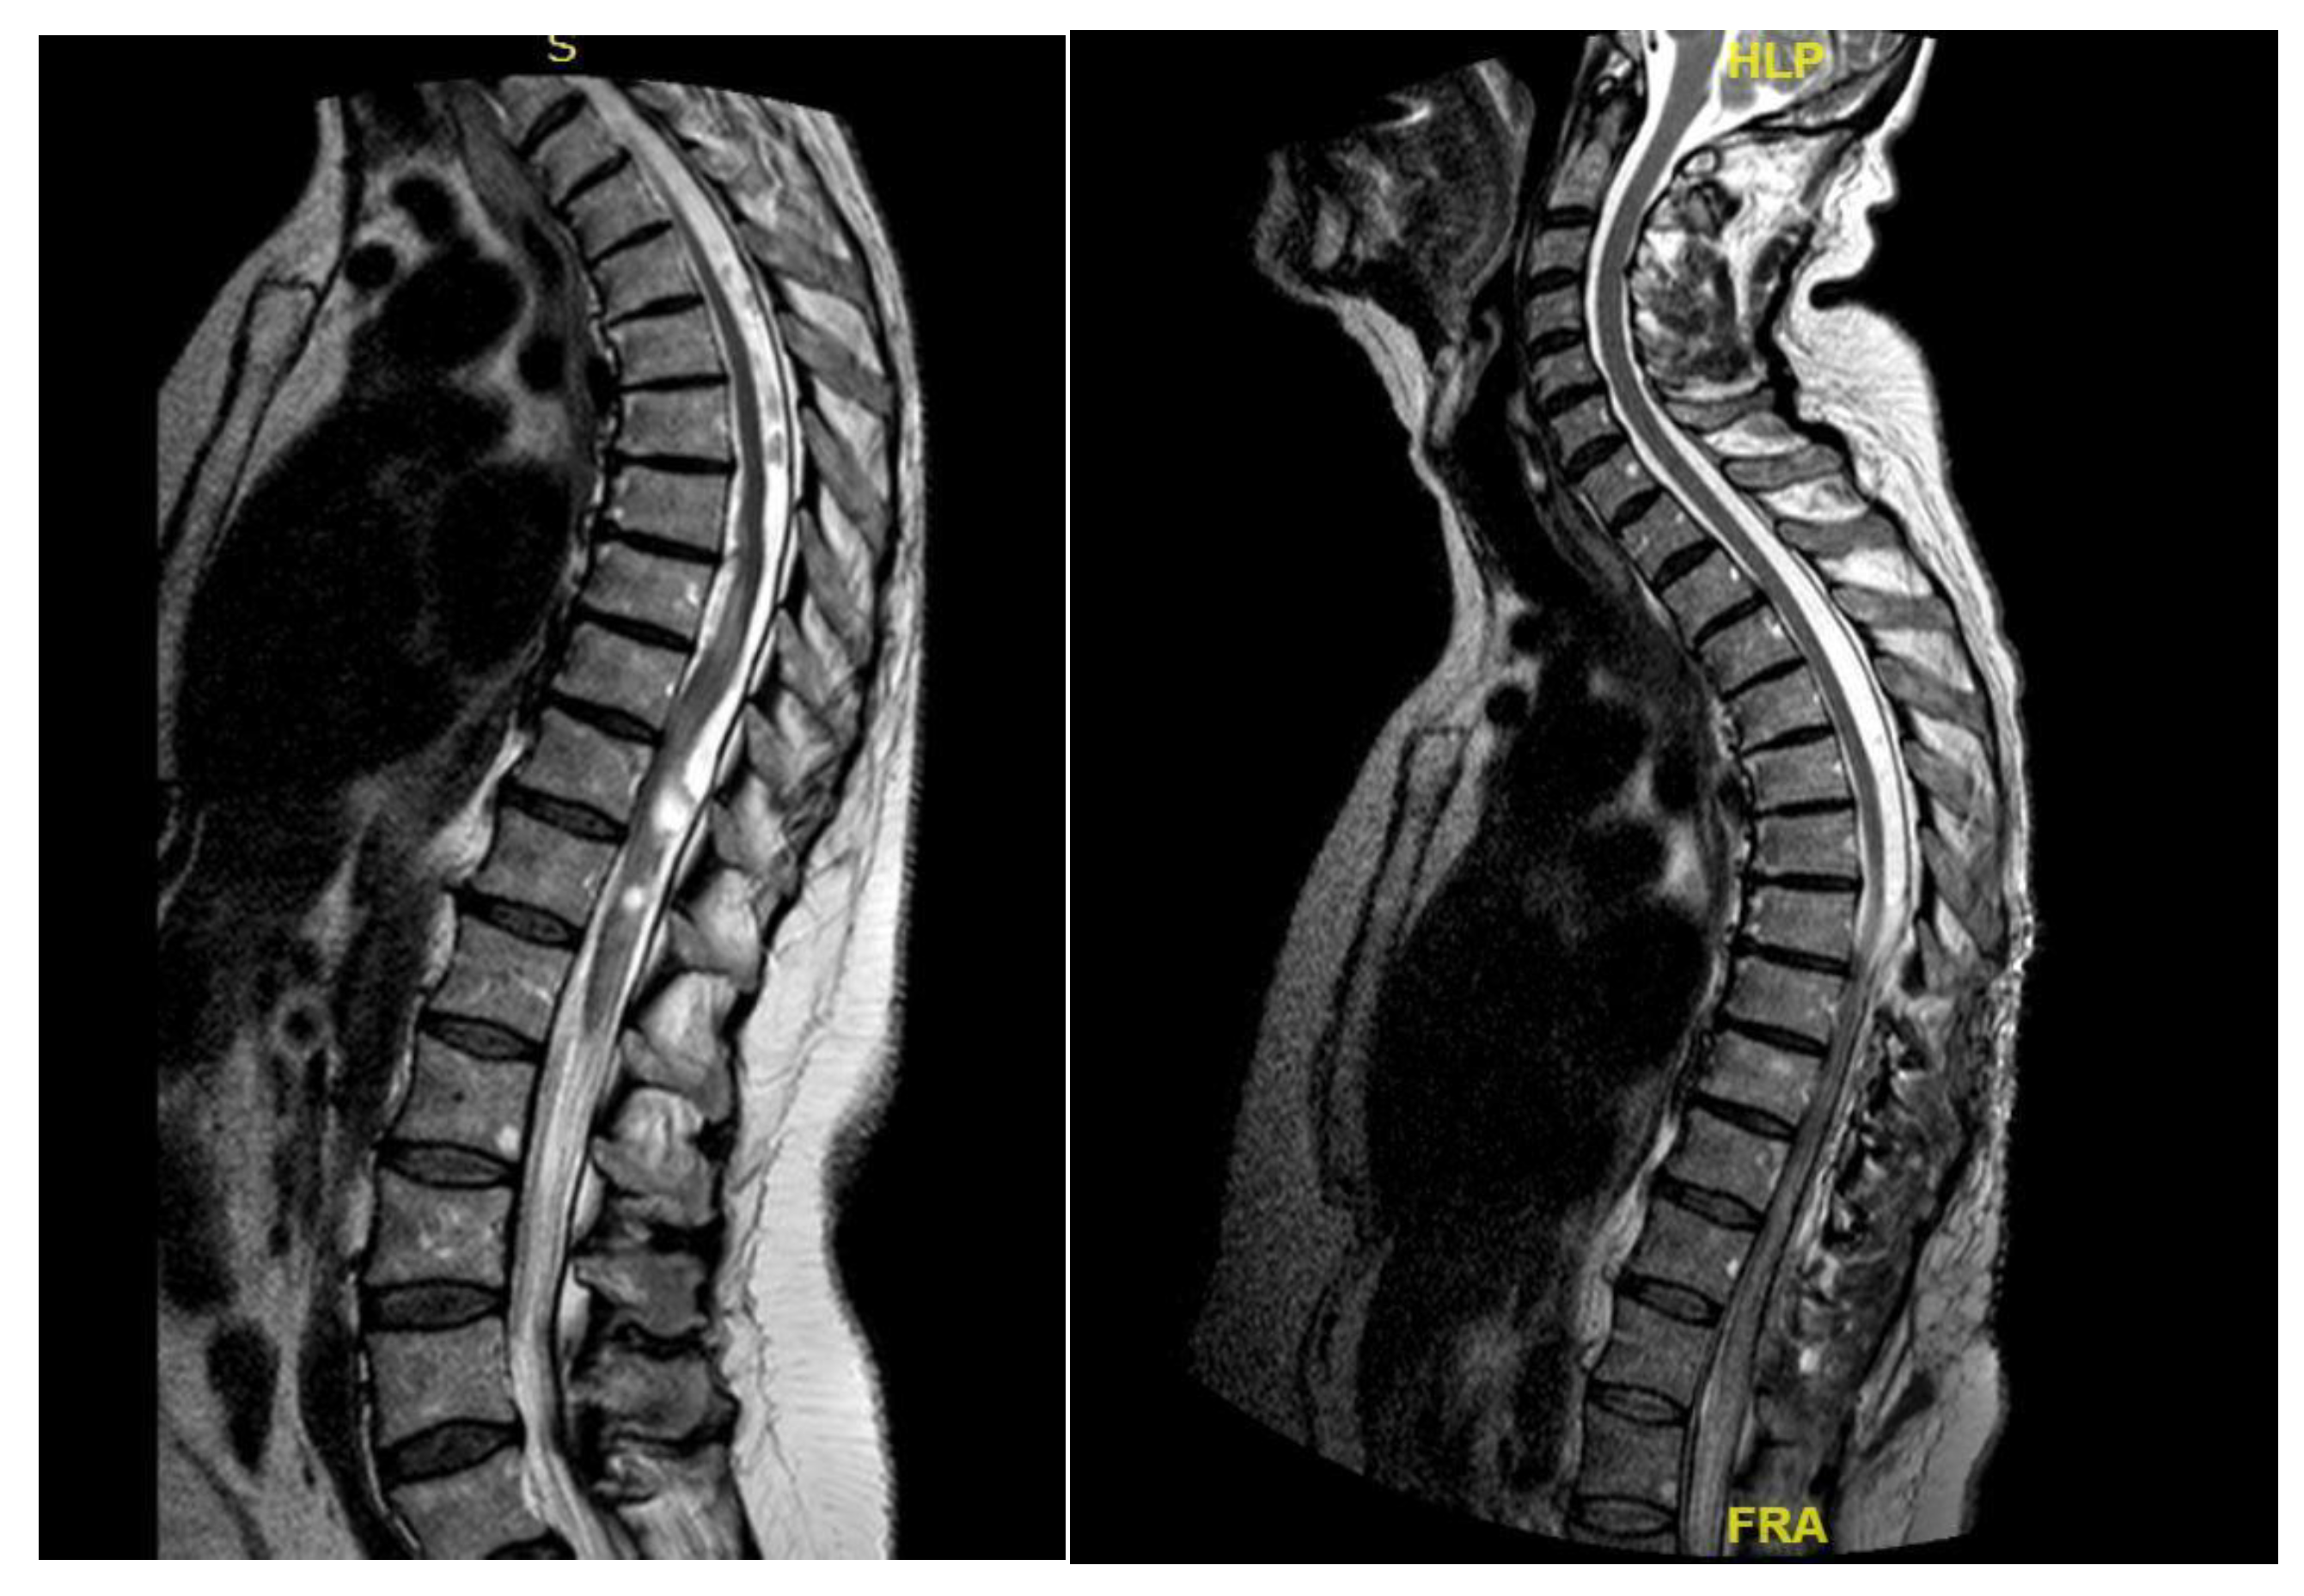

A 43-year-old woman, following a microdiscectomy at D8-D9 and 2 years of symptom relief, developed sensory deficits and gait difficulties. Neurological evaluation revealed right lower limb weakness and an ataxic gait. Pre-operative MRI identified an intradural cyst at D8-D9 [Figure 6]. Surgical intervention involved a right hemilaminectomy (D7-D9) to remove the cyst and resolve arachnoid adhesions. Histology confirmed an arachnoid cyst. An initial post-operative improvement was followed by symptoms worsening, including new onset of syringomyelia.

Figure 6. Case 4: pre-operative MRI illustrating a ventral intradural cyst.

Figure 8. Case 4: post-operative MRI showing the reduction of syringomielic size.